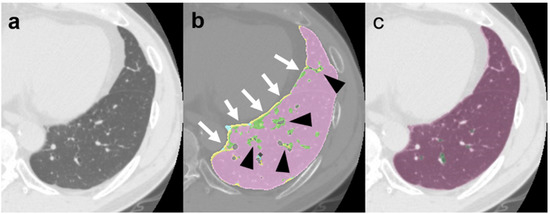

Article

We investigated the feasibility of a new deep-learning (DL)-based lung analysis method for the evaluation of interstitial lung disease (ILD) by comparing it with evaluation using the traditional computer-aided diagnosis (CAD) system and patients’ clinical outcomes. We prospectively included 104 patients (84 with [...] Read more.

We investigated the feasibility of a new deep-learning (DL)-based lung analysis method for the evaluation of interstitial lung disease (ILD) by comparing it with evaluation using the traditional computer-aided diagnosis (CAD) system and patients’ clinical outcomes. We prospectively included 104 patients (84 with and 20 without ILD). An expert radiologist defined regions of interest in the typical areas of normal, ground-glass opacity, consolidation, consolidation with fibrosis (traction bronchiectasis), honeycombing, reticulation, traction bronchiectasis, and emphysema, and compared them with the CAD and DL-based analysis results. Next, we measured the extent of ILD lesions with the CAD and DL-based analysis and compared them. Finally, we compared the lesion extent on computed tomography (CT) images, as measured with the DL-based analysis, with pulmonary function tests results and patients’ overall survival. Pearson’s correlation analysis revealed a significant correlation between DL-based analysis and CAD results. Forced vital capacity was significantly correlated with DL-based analysis (r = 0.789, p < 0.001 for normal lung volume and r = −0.316, p = 0.001 for consolidation with fibrosis volume). Consolidation with fibrosis measured using DL-based analysis was independently associated with poor survival. The lesion extent measured using DL-based analysis showed a negative correlation with the pulmonary function test results and prognosis. Full article

Show Figures

Figure 1